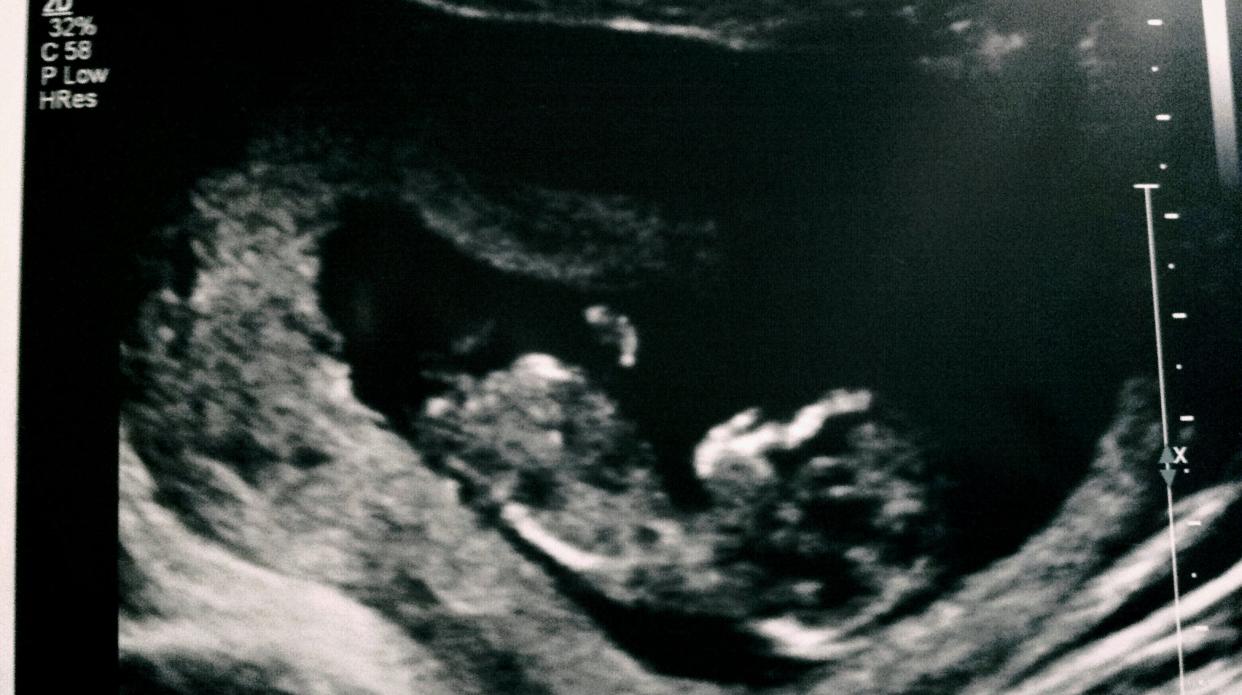

Had a 12 week ultrasound and tech very confident its a boy, what do you think?? :-)

Can't see the nub on those pics, but if tec told you it was a boy, then it probably is! :)

In the second pic there is something there sticking out...the pic is a lil large, have to move the sliding bar over to see the whole pic. :-)

I think boy. I see a nub sticking up in the second picture.

Looks boy in the second pic.

I found another shot...maybe it will help some...I will be having another ultrasound in a few weeks so maybe I will have better shots then. :-)

I can see why they predicted boy....but it's soooo early. I just wouldn't go shopping or painting until a 16 week or greater u/s shot :) Good luck!

UPDATE: Confirmed Boy, 16weeks 2days :-)